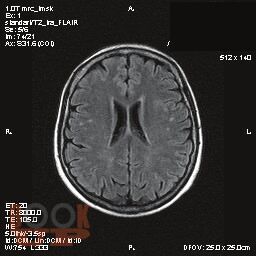

В монографии рассматриваются особенности проявления и методы диагностики когнитивной дисфункции у пациентов с сахарным диабетом 1 типа. Описан комплекс современных методов исследования и диагностики когнитивных нарушений при сахарном диабете 1 типа. Систематизированы сведения в отношении влияния когнитивной дисфункции на качество жизни пациентов с сахарным диабетом 1 типа. Представлен алгоритм ведения диспансерных пациентов с сахарным диабетом 1 типа в плане диагностики когнитивной дисфункции.

В монографии рассматриваются особенности проявления и методы диагностики когнитивной дисфункции у пациентов с сахарным диабетом 1 типа. Описан комплекс современных методов исследования и диагностики когнитивных нарушений при сахарном диабете 1 типа. Систематизированы сведения в отношении влияния когнитивной дисфункции на качество жизни пациентов с сахарным диабетом 1 типа. Представлен алгоритм ведения диспансерных пациентов с сахарным диабетом 1 типа в плане диагностики когнитивной дисфункции. Книга адресована студентам, ординаторам, преподавателям, врачам-эндокринологам, неврологам, терапевтам.